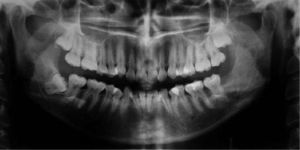

Tras 10 meses de seguimiento clínico-radiográfico, con la presencia de una cánula de descompresión cuya longitud es reducida gradualmente, se constata la reducción casi total de la lesión quística ameloblástica, por lo que se efectúa cirugía de enucleación y curetaje de la cavidad residual, además de exodoncia del tercer molar involucrado (figs. 4 y 5) 15.